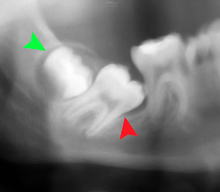

For partially impacted teeth in those over 20 year of age, the most common pathology seen, and the most common reason for wisdom teeth removal, is pericoronitis or infection of the gum tissue over the impacted tooth. The bacteria associated with infections include Peptostreptococcus, Fusobacterium, and Bacteroides bacteria. The next most common pathology seen is cavities or tooth decay. Fifteen percent of people with retained wisdom teeth exposed to the mouth have cavities on the wisdom tooth or adjacent second molar due to a wisdom tooth. The rate of cavities on the back of the second molar has been reported anywhere from 1% to 19% with the wide variation attributed to increased age.[10]

In five percent of cases, advanced periodontitis or gum inflammation between the second and third molars precipitates the removal of wisdom teeth.[3]:141[4] Among patients with retained, asymptomatic wisdom teeth, roughly 25% have gum infections (periodontal disease).[11]:ch13 Teeth with periodontal pockets of greater than 5mm have tooth loss rates that start at 10 teeth lost per 1000 teeth per year at 5mm to a rate of 70 teeth lost per year per 1000 teeth at 11mm.[12]:57 The risk of periodontal disease and caries on third molars increases with age with a small minority (less than 2%) of adults age 65 years or older maintaining the teeth without caries or periodontal disease and 13% maintaining unimpacted wisdom teeth without caries or periodontal disease.[13] Periodontal probing depths increase over time to greater than 4 mm in a significant proportion of young adults with retained impacted wisdom teeth which is associated with increases in serum inflammatory markers such as interleukin-6, soluble intracellular adhesion molecule-1 and C-reactive protein.[14]